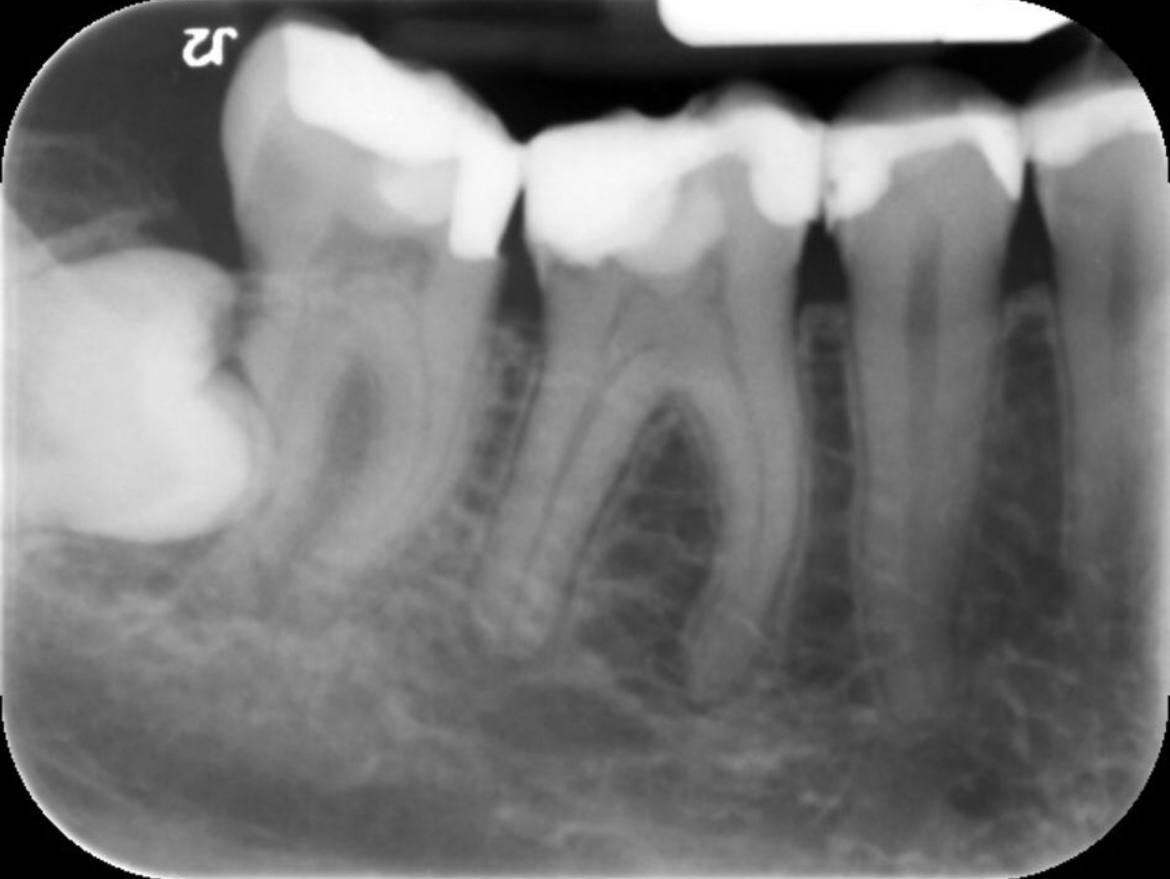

Wie kan mij helpen. Na lang uitstellen heb ik toch maar een afspraak gemaakt bij de kaakchirurg ingepland om mijn verstandskies eruit te halen die dwars ligt. (23 februari) De kiest daarnaast blijft staan en in de andere kies die daar naast staat zou een ontsteking zitten in de wortelpunt. Ik schrok heel erg van de kosten dus twijfel nu wat te doen. Of een wortelkanaalbehandeling of door de vele vullingen die al in deze tand zitten deze ook maar te trekken. Ik ben erg onzeker over mijn gebit door alle vullingen die ik heb in met name de kiezen. Aan de andere kant van mijn gebit is namelijk ook al een kies getrokken omdat deze gewoon heel zwak was en constant afbrak.

Ik hoop dat ik nog wel even met mijn tanden kan doen. Wat vind je op dit moment van de foto?

Je zou dus wel een wortelkanaalbehandeling doen ipv trekken (de eerste kies)

Zie je een grote ontsteking? Of kan dit nog behandeld worden met een antibiotica kuur.

Verstand kies verwijderen, wkb 46 ( eerste grote kies flinke ontsteking niet met AB kuur goed te krijgen) later kroon ( als u kiest voor behoud met vaste voorzieningen).....